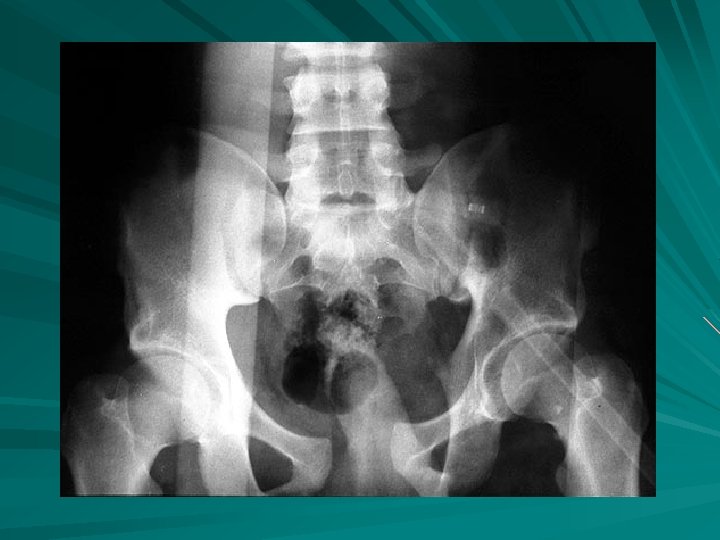

Zoomed lower pelvis demonstrating multiple fractures (arrows).